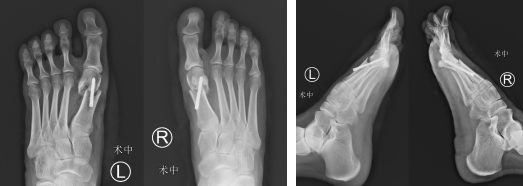

次日,石荣剑副院长、曹广超主任、王岩岩医生手术团队为患者进行了双足拇外翻截骨矫形术(微创)。首先行左足拇外翻截骨矫形术,取第1跖趾关节背外侧纵形切口长约0.5cm,钝性分离至骨面,使用微创专用勾刀进行拇收肌松解术,内翻第1趾见拇外翻角度较前减小,仍大于正常;将跖骨头向外侧、足底推移,并进行内固定,透视确认内固定位置、长度良好,拇外翻角度恢复正常。同法处理右足拇外翻畸形,手术顺利。

术前外形

术前外形和切口设计两个小切口,一个0.5cm,一个不到1cm

术中截骨空心钉固定

术后即刻外观